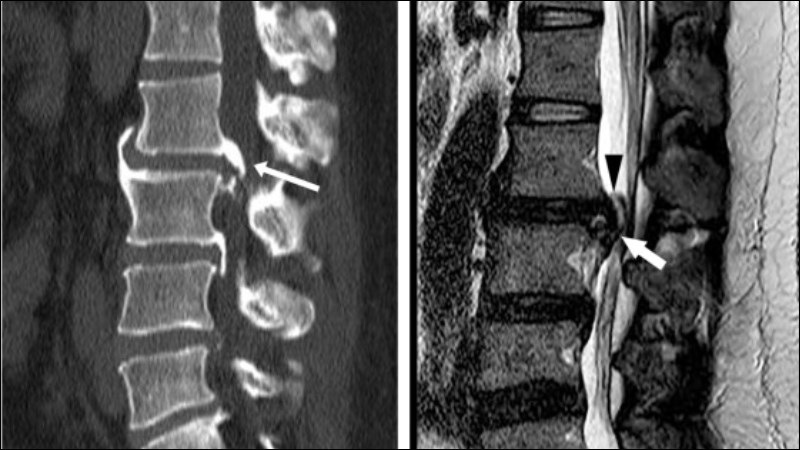

Trong trường hợp nghi ngờ người bệnh mắc thoát vị đĩa đệm nội xốp, các xét nghiệm chẩn đoán hình ảnh có thể góp phần quan trọng giúp bác sĩ chẩn đoán xác định bệnh, chẳng hạn như:

- Chụp X-quang: nhằm loại trừ các nguyên nhân khác gây đau lưng trên người bệnh, đồng thời khảo sát sự xuất hiện của các nốt schmorl trên đốt sống.

- Chụp CT: là xét nghiệm quan trọng giúp bác sĩ đánh giá các tổn thương xung quanh cột sống và phân biệt tình trạng thoát vị đĩa đệm nột xốp hay thoát vị đĩa đệm.

- Chụp cộng hưởng từ MRI: cho phép bác sĩ khảo sát một cách chi tiết mức độ tổn thương điax đệm, tủy sống, các mô xốp bên trong đốt sống.